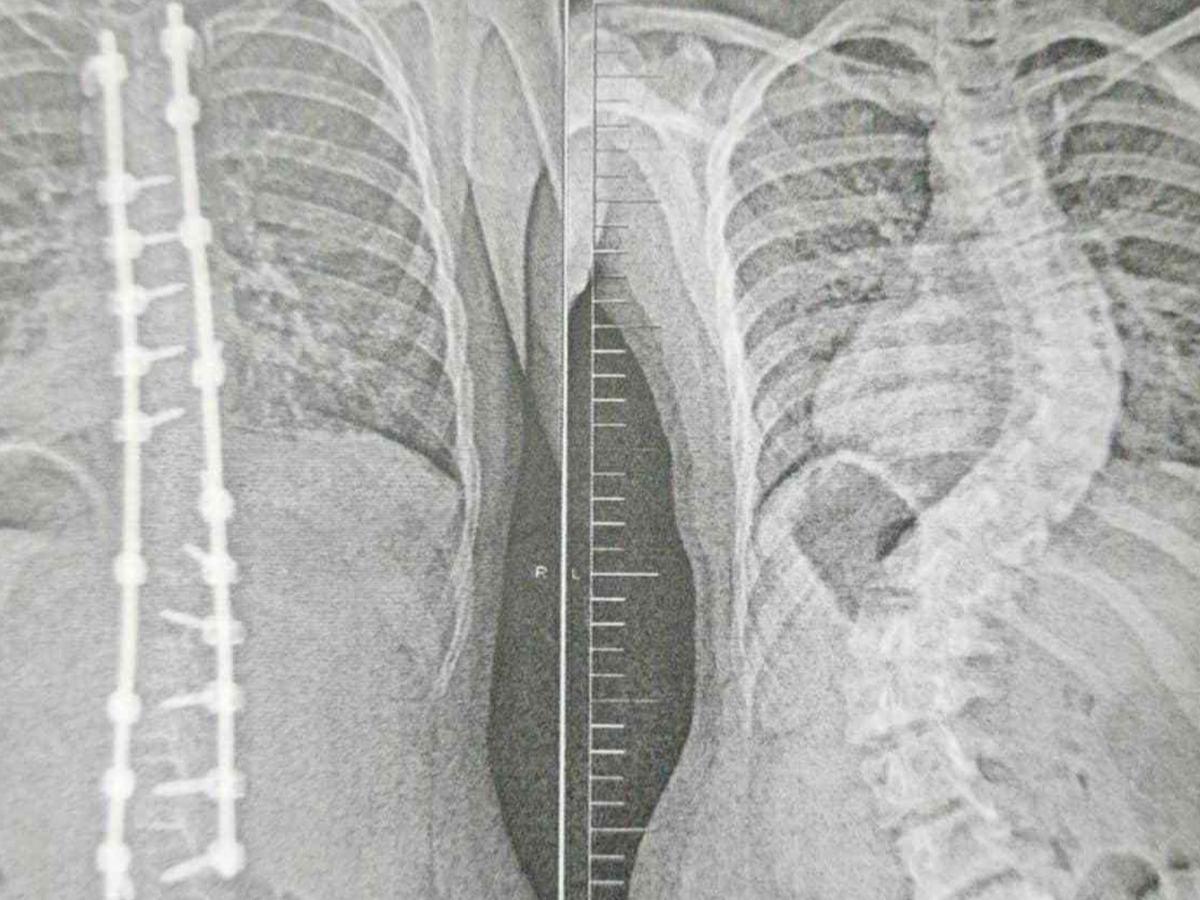

Under a year ago, my world was shaken when she was diagnosed with idiopathic adolescent scoliosis. Despite my hopes and efforts to slow its progression, her spine has curved to a devastating 60+ degrees, leaving her with only one option: life-changing surgery to protect her organs and her future.